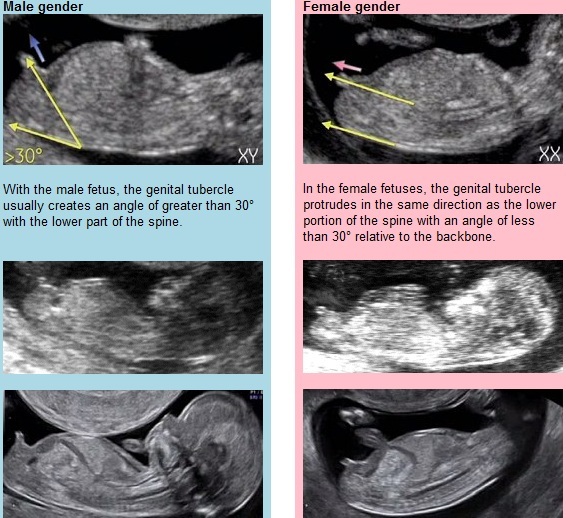

I didn't get it either IrnBrufan until I read this:-

April 2017 #4 More baby scans, less morning sickness!

I went for my scan yesterday and am only 11 weeks, but it's such a relief to know everything is ok! It's great to see everyone else's scan pics. I'm back for another in a couple of weeks so I've no pic until then! I'll be trying the nub theory though, it'll be interesting to see if it works!

Thanks celen - maybe it's the angle of my scan picture but I can't any comparison between it and the examples Hahahaha